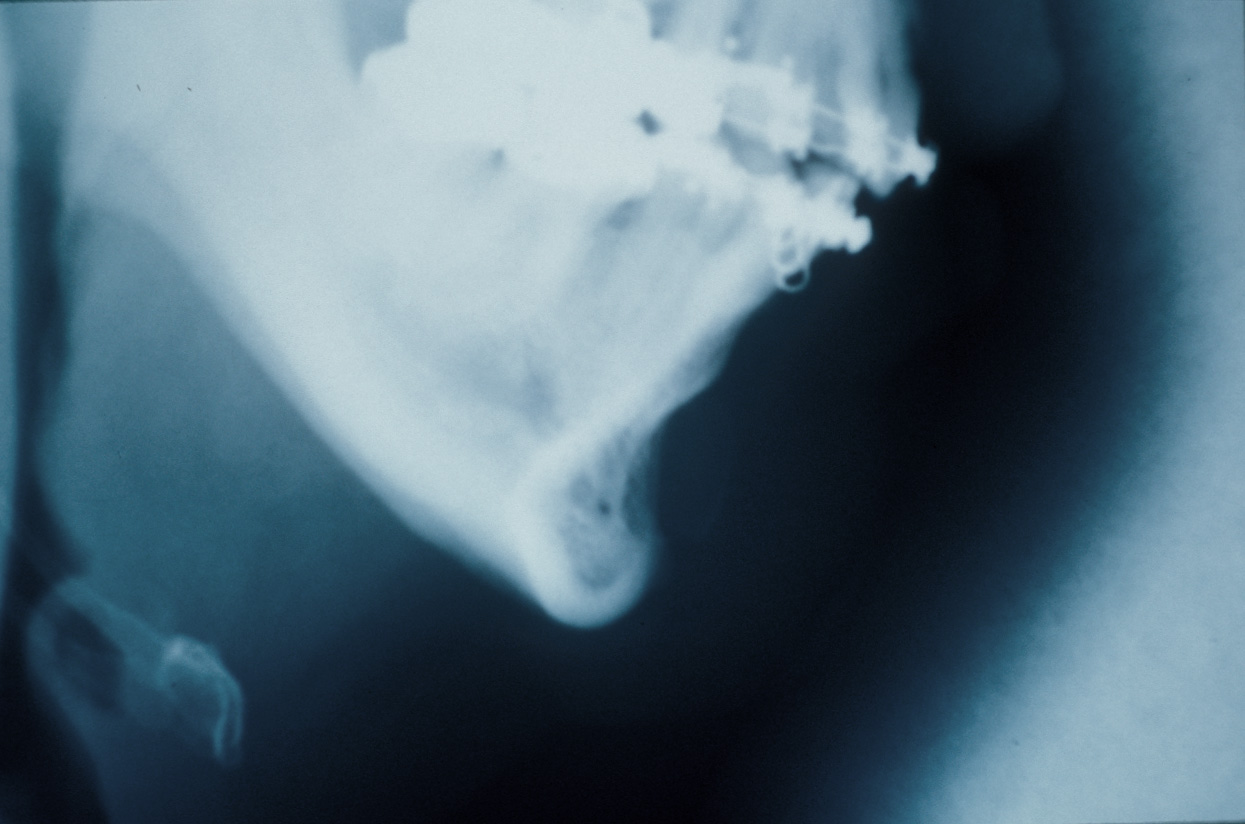

Intraoral sliding genioplasty done for a 10mm bone advancement. The result is taken 8 years after the surgery. The 3D CT scan, however, was taken just months after the surgery.